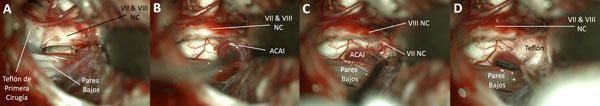

Figura 9. RM con T2 pesado y T1 con gadolinio donde se observa una estructura vascular que impronta desde la región inferior de la salida real del nervio facial en la cisterna del ángulo ponto cerebeloso izquierda (A y B). Luego de disecar y reclinar el flóculo, se orienta el microscopio hacia el tronco cerebral y se observa el origen real del nervio con la impronta vascular referida (C, D, E y F). Se interpone teflón y se corrobora con endoscopio de 30 grados la efectiva descompresión (F).

Figura 10. Recirugía: en la primera cirugía (otro equipo), se colocó el teflón muy distal.